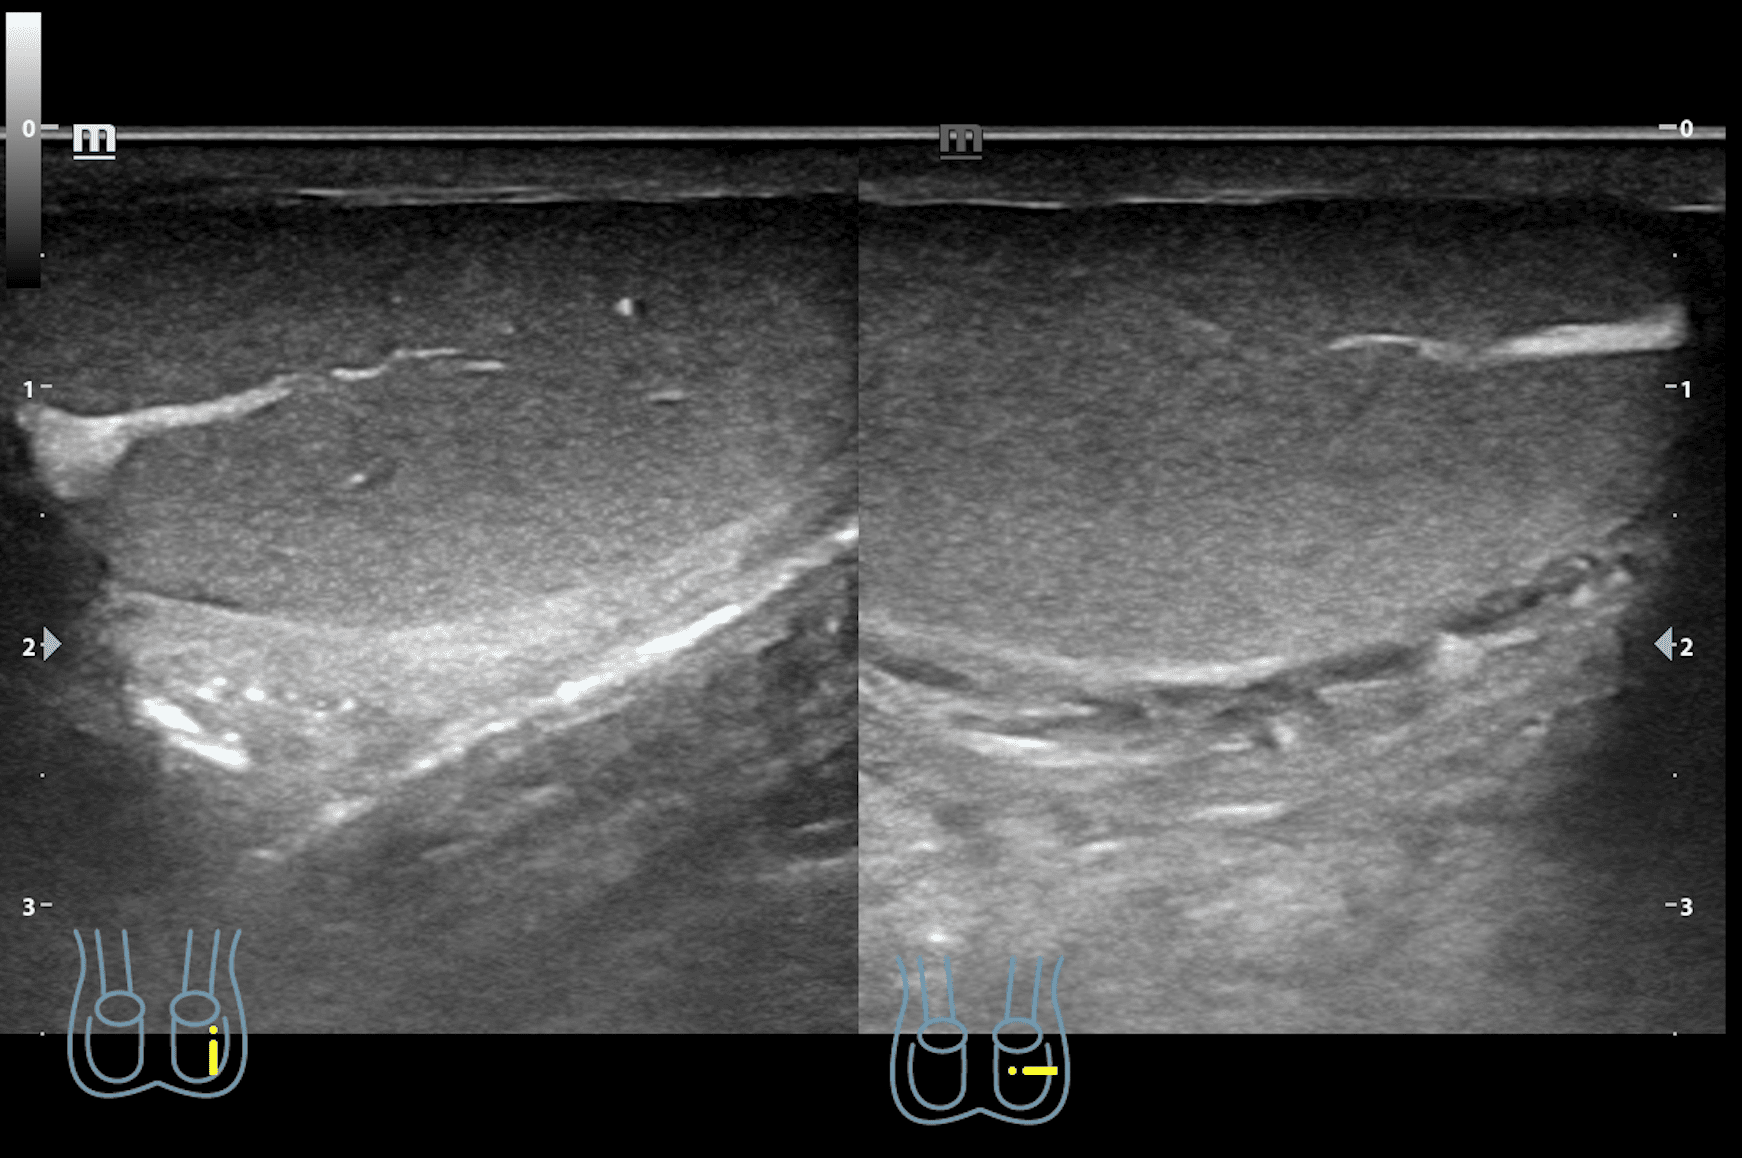

A nivel de escroto derecho, se observa imagen heterogénea con contenido intestinal compatible con hernia inguino-escrotal derecha. Testículos de aspecto normal.